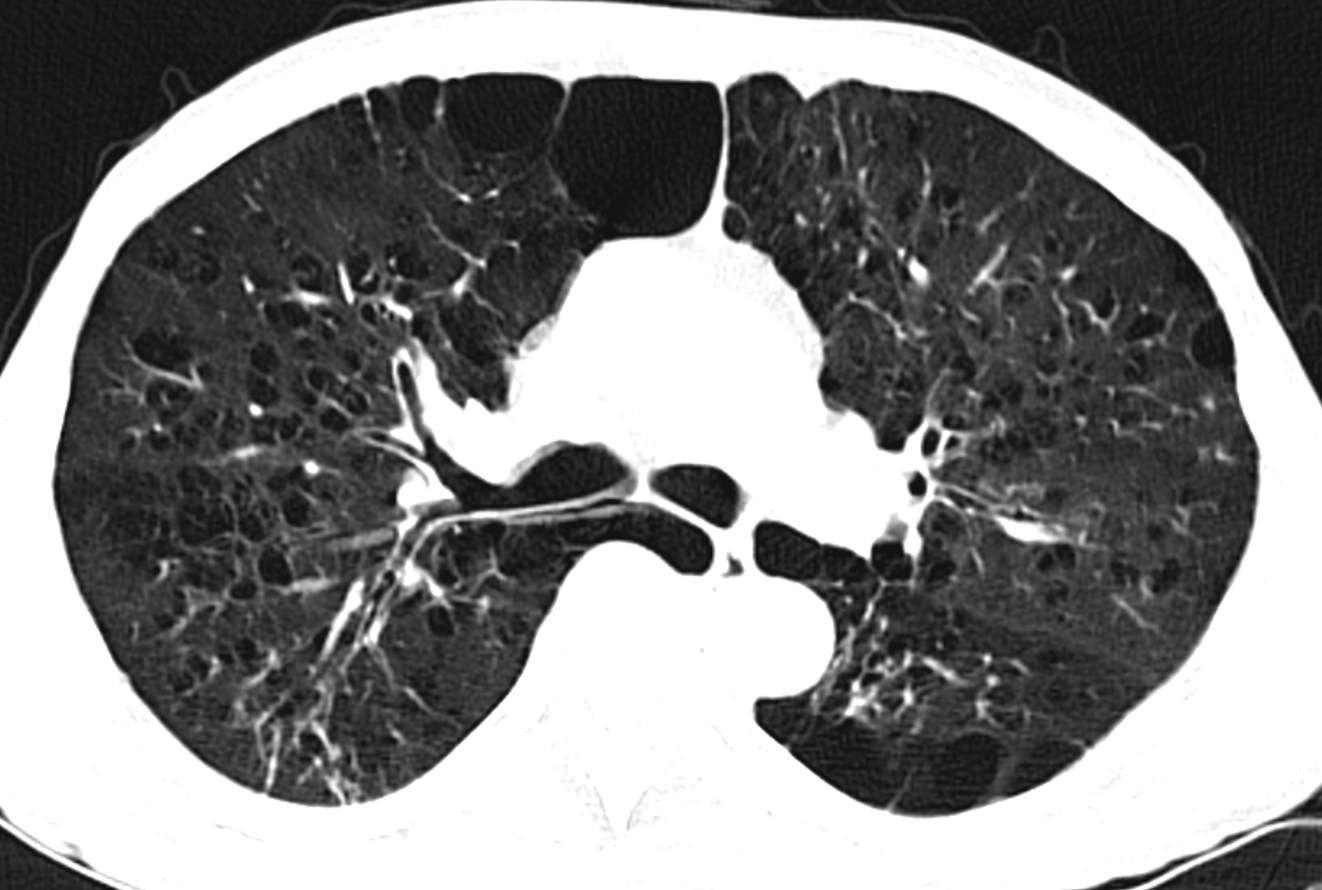

因CT明显异常而复诊。

因患者有肺大泡,肺功能存在一定禁忌。